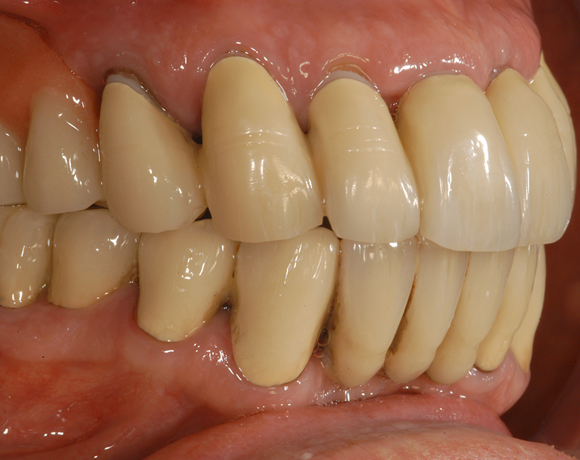

Im vorliegenden Patientenfall musste eine komplette Neukonstruktion der Oberkieferversorgung vorgenommen werden, da auf Grund parodontaler Probleme die Seitenzahnbrücken 15 – 17 und 25 – 27 nicht mehr zu halten waren. Die verbliebenen acht Frontzähne bzw. Prämolaren waren auch parodontal vorgeschädigt und es war ungewiss wie lange sie einzelne noch halten lassen. Um nicht bei jedem Verlust eines der Restzähne eine Neukonstruktion zu brauchen, hat man sich für eine Teleskopprothese entschieden. Für den Patienten war es allerdings nicht vorstellbar goldfarbene Primärteile im Mund zu haben, so wurde der Versuch unternommen diese aus e.max Press und Galvano Sekundärteilen herzustellen.